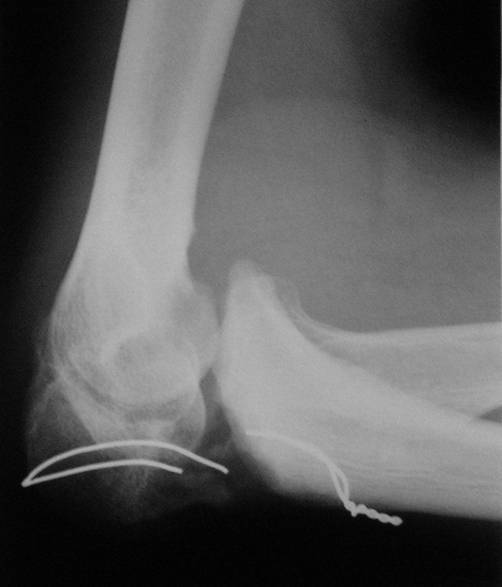

Коллеги! Сделана операция. Убрана рубцовая ткань, освежены концы до "кровяной росы", произведен релиз локтевого отростка и заднего отдела сустава - прошел до венечного отростка. После адаптации отломков выяснилось, что полное сопоставление происходит только на 1/4 периметра. Уложены аутотрансплантаты взятые из крыла подвздошной кости. Приведена схема. Через локтевой отросток проведены две спицы с упорными площадками с разбросом в 1 см, закрепленные на отдельном полукольце. Дана компрессия. Пятые сутки, рана заживает первичным натяжением. Выписываю. На 14 сутки буду пробовать движения.

Николай.